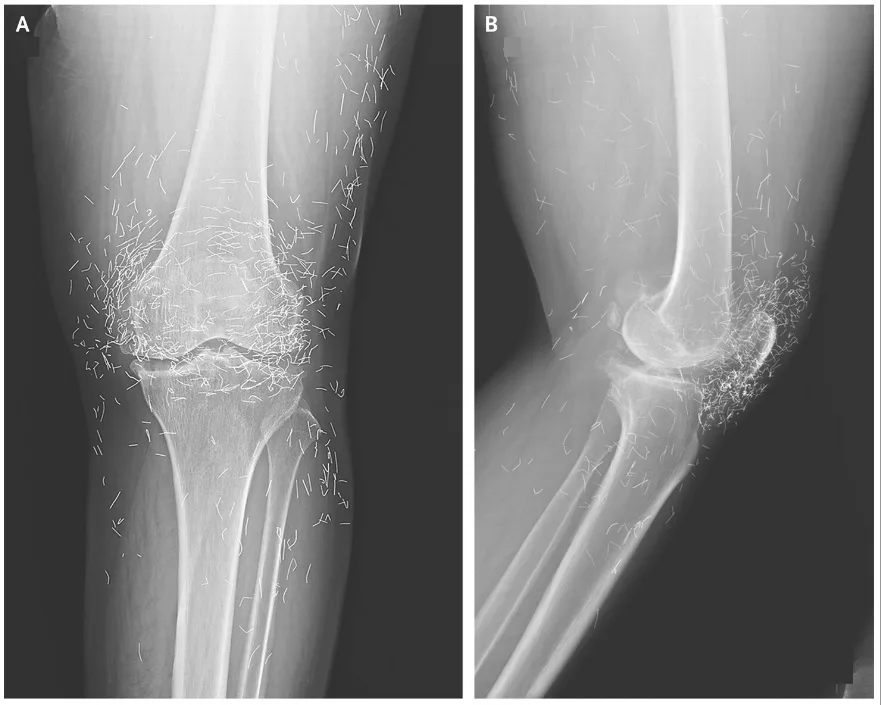

一位患有膝关节骨关节炎的女性,在服用止痛药后开始出现严重的胃部不适,于是开始定期接受针灸治疗。

但针灸治疗之后,她的膝盖也开始剧烈疼痛,遂前往医院就诊。X光片显示,她的关节和胫骨部分区域骨组织增厚并形成骨刺。此外,双膝关节周围还可见数百个细小的斑点。原来,这位女性的针灸师在治疗过程中故意将金线留在她的膝盖内。在其他一些案例中,这些金线在体内游走时,会导致囊肿和组织损伤。